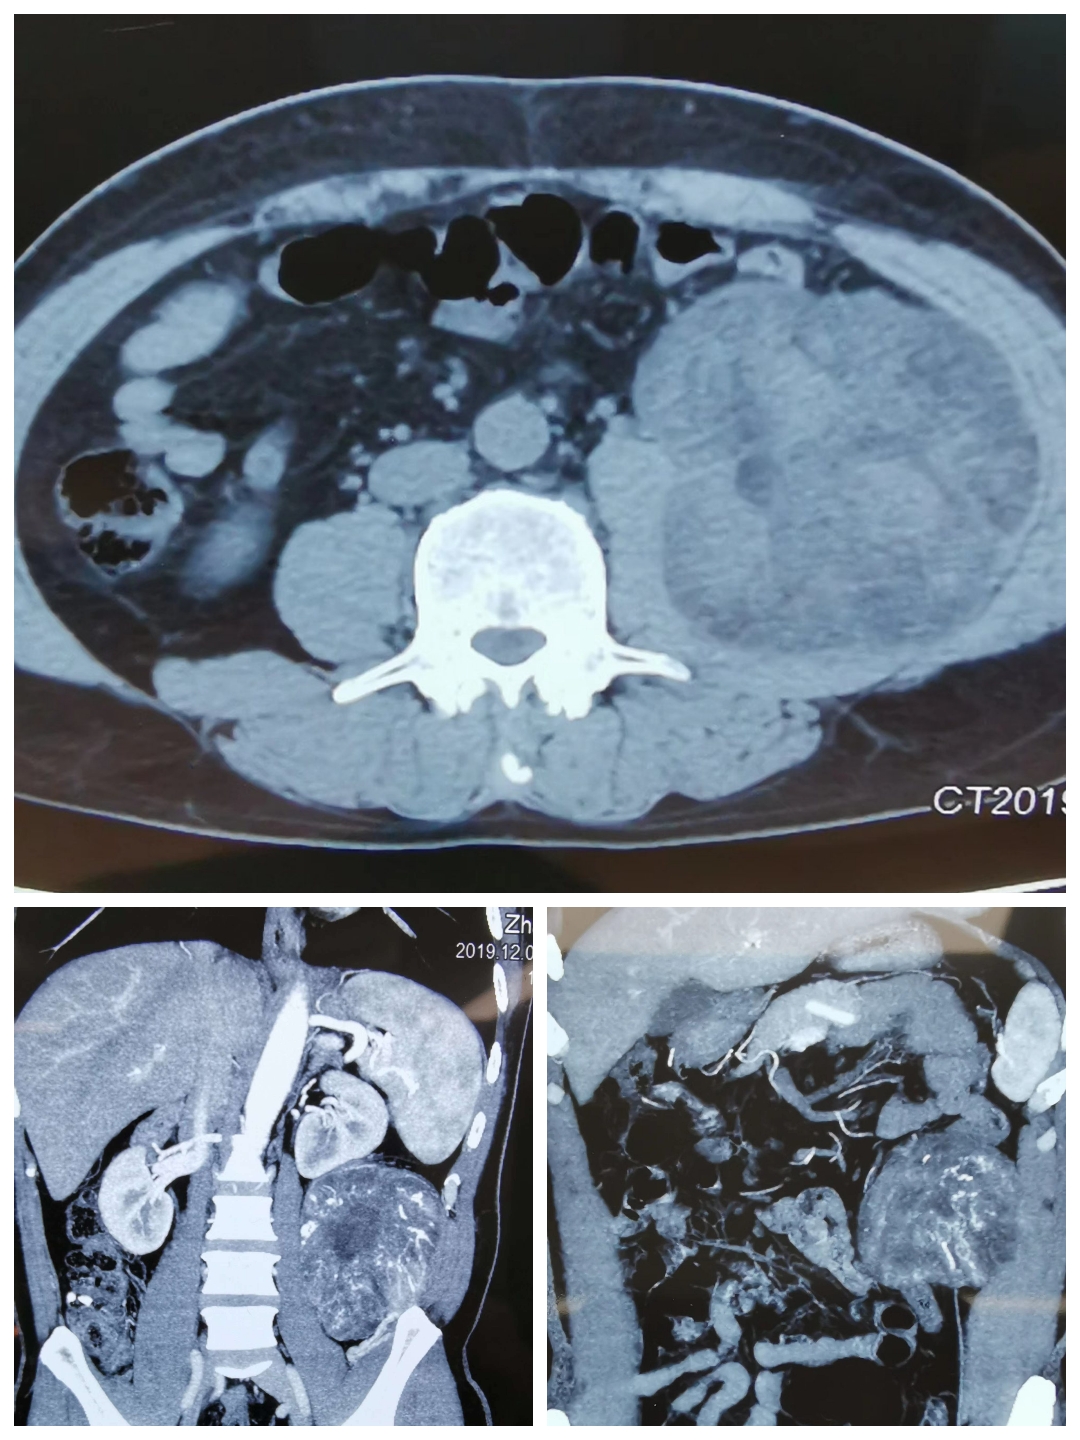

2019年12月22日,是我国传统二十四节气中的冬至,在家家户户团聚在一起包饺子、吃饺子之际,成人快手 外二科(结直肠肛门疾病专业、综合外科)在麻醉手术室、检验科等相关兄弟科室的配合下,成功完成一例腹膜后巨大肿瘤切除术。患者男性,主因“左侧腹部憋胀不适6月”而入院。完善腹部CT回报:左中腹部腹膜后巨大占位性病变,考虑脂肪肉瘤可能性大。患者近期有发热表现,不排除肿瘤出血、坏死可能。经过充分的术前评估,翟春宝主任决定限期行根治性手术治疗。

手术标本,大小约13cm×13cm×15cm,包膜完整,脂肪肉瘤可能